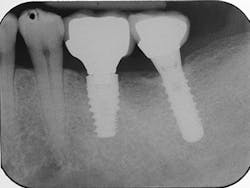

The most critical aspect of any implant system is the interface between the implant fixture and its surrounding bone (figures 1-5). Integration between the fixture and its surrounding bone is the foundation of modern implant dentistry. There is little we can do to modulate bone healing, but we can modify the implant fixture itself.

Figures 1-5: Figures 1 through 4 illustrate, respectively, a seven-year follow-up visit and a three-year follow-up visit of two different implant systems. Implant No. 22 (figure 5) shows peri-implant radiolucency following functional loading, indicating fibroencapsulation and loss of integration into bone, necessitating removal.